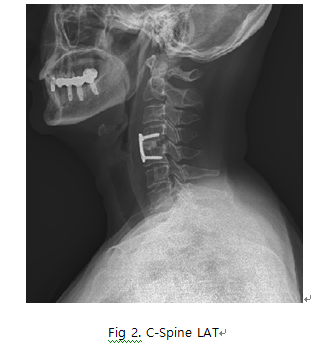

C-Spine Lateral

1. 목적

- Odontoid process, C2~C7의 body fracture, spinous process의 fracture, narrowing of disc space, C1의 anterior and posterior arch의 fracture를 관찰한다.

- spine의 정열이 바른지 본다.

6) 영상 결과